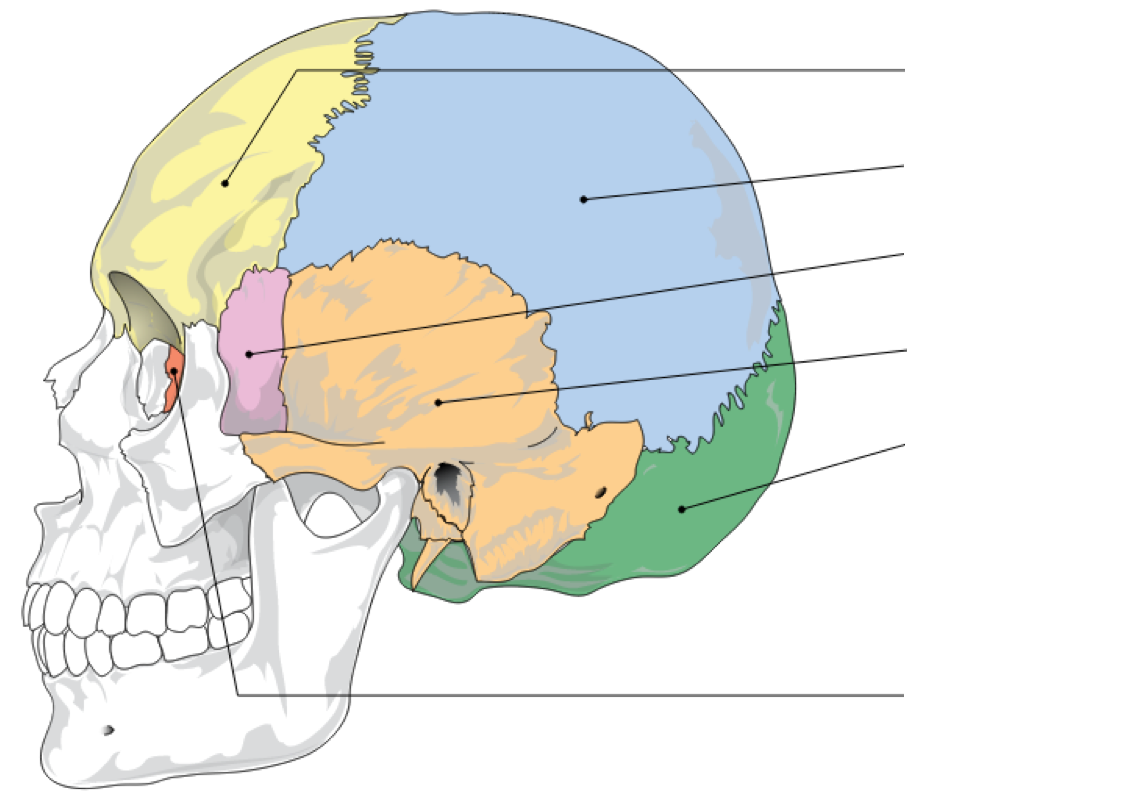

Label image

Label the mandible